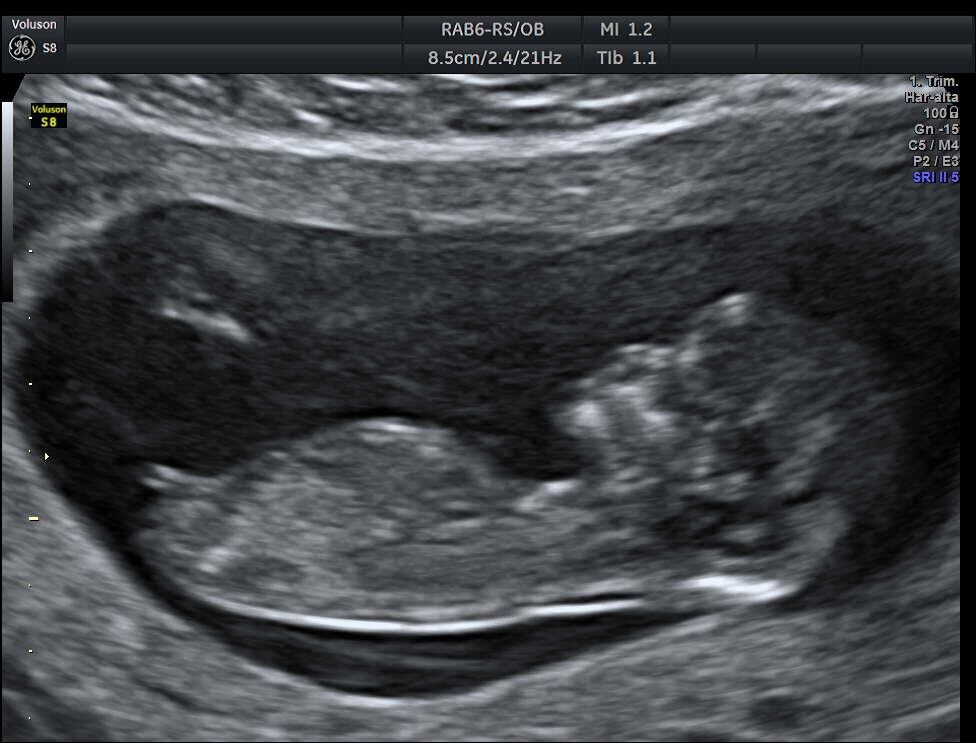

Sí, la fecha la teníamos pensada para estos días, de hecho desde antes de que se diera la pandemia. Pensamos en pasarla para setiembre, pero Caro está embarazada (tiene tres meses), así que cuando nos dimos cuenta de la llegada del bebé decidimos mantener esta fecha.

A Caro la conocí en diciembre y para mí fue amor a primera vista. Ella es superinteligente, supersensible, muy guapa y me encantó desde el principio, así que las cosas se fueron dando. Ella tiene 31 años y yo voy para 28 y estamos en una edad bonita para tomar decisiones serias. Primero nos fuimos a vivir juntos y nos encantó todo, nos llevamos muy bien y pues le propuse matrimonio y aquí estamos ya casados y esperando que en la próxima cita al doctor nos digan si es niño o niña.

El bebé está para el 31 de diciembre o el 1° de enero así que nos tocará pasar Año Nuevo en esa labor. Tengo que aprender a cambiar pañales porque en mi vida nunca he cambiado un solo pañal.